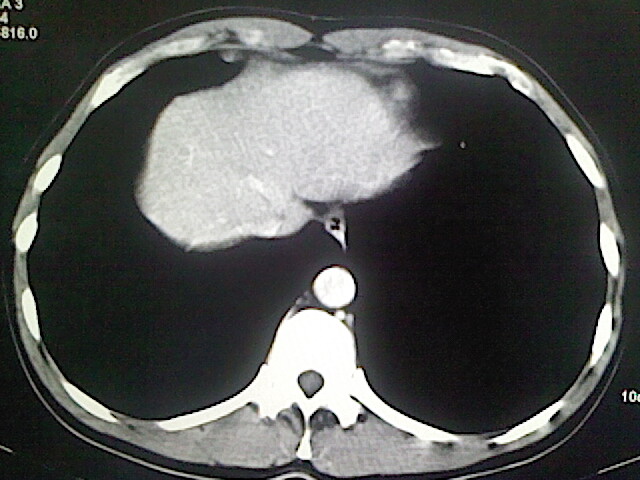

以下是引用卜一在2009-3-14 9:49:00的发言:[br]胆囊萎缩,胆囊壁不规则增厚,内部结构模糊,增强明显强化。另:肝左叶外侧段肝囊肿。支持:慢性胆囊炎!高度可疑:胆囊癌!

以下是引用余辉在2009-3-14 8:48:00的发言:[br]1)慢性胆囊炎。2)肝左叶外侧段肝囊肿。3)脂肪肝。[br]支持,胆囊萎缩,密度增高,不知b超具体有何提示,钙胆汁?结石?

以下是引用jiangjing在2009-3-14 10:18:00的发言:[br]1)慢性胆囊炎。2)肝左叶外侧段肝囊肿。3)脂肪肝。4.】建议行肝功能检查